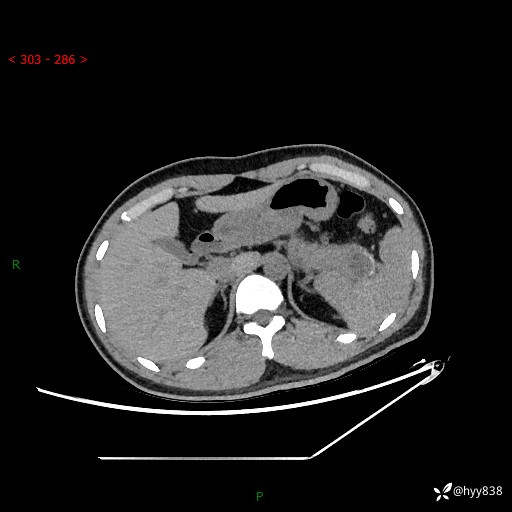

【患者信息】:31岁/男

【主诉】:间断性左下腹疼痛10天

【现病史及既往史】: 患者10余天前无明显诱因出现左下腹部疼痛,呈间断性,无恶心,呕吐,无黄疸,腹泻症状,于当地医院就诊,行腹部C提示:胰腺尾部占位。2型糖尿病。现患者为求手术治疗,门诊以“胰腺肿物”收入院。 患者起病来,一般情况可,大小便正常,体重体力未见明显减轻。

【检查】:胰腺CT平扫+增强